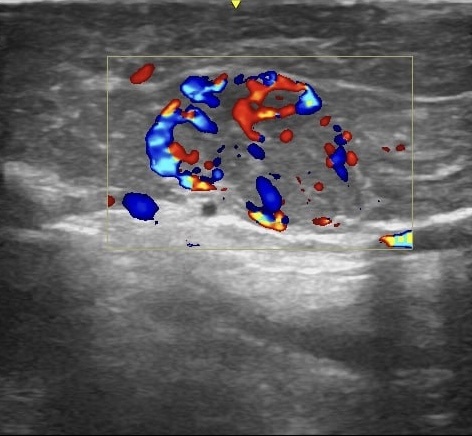

🩸 Изображение 2 – цветное доплеровское картирование выявляет активный кровоток, что подтверждает васкуляризацию опухоли. Такие образования активно накапливают контрастный препарат, что важно учитывать при выборе тактики лечения.